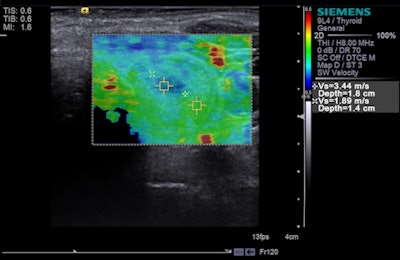

StarVIBE is a new pulse sequence that enables free-breathing, contrast-enhanced liver imaging for patients who are unable to easily manage breath-holding, such as those who are old, very ill, or young. Meanwhile, TWIST-VIBE is intended for more accurate contrast imaging in dynamic liver MRI scans for all patients and lesions, allowing faster liver imaging with full 4D coverage.

With Siemens' StarVIBE technology, no breath-hold is needed. The images above and below show the increase in image quality with StarVIBE. Images courtesy of Siemens.